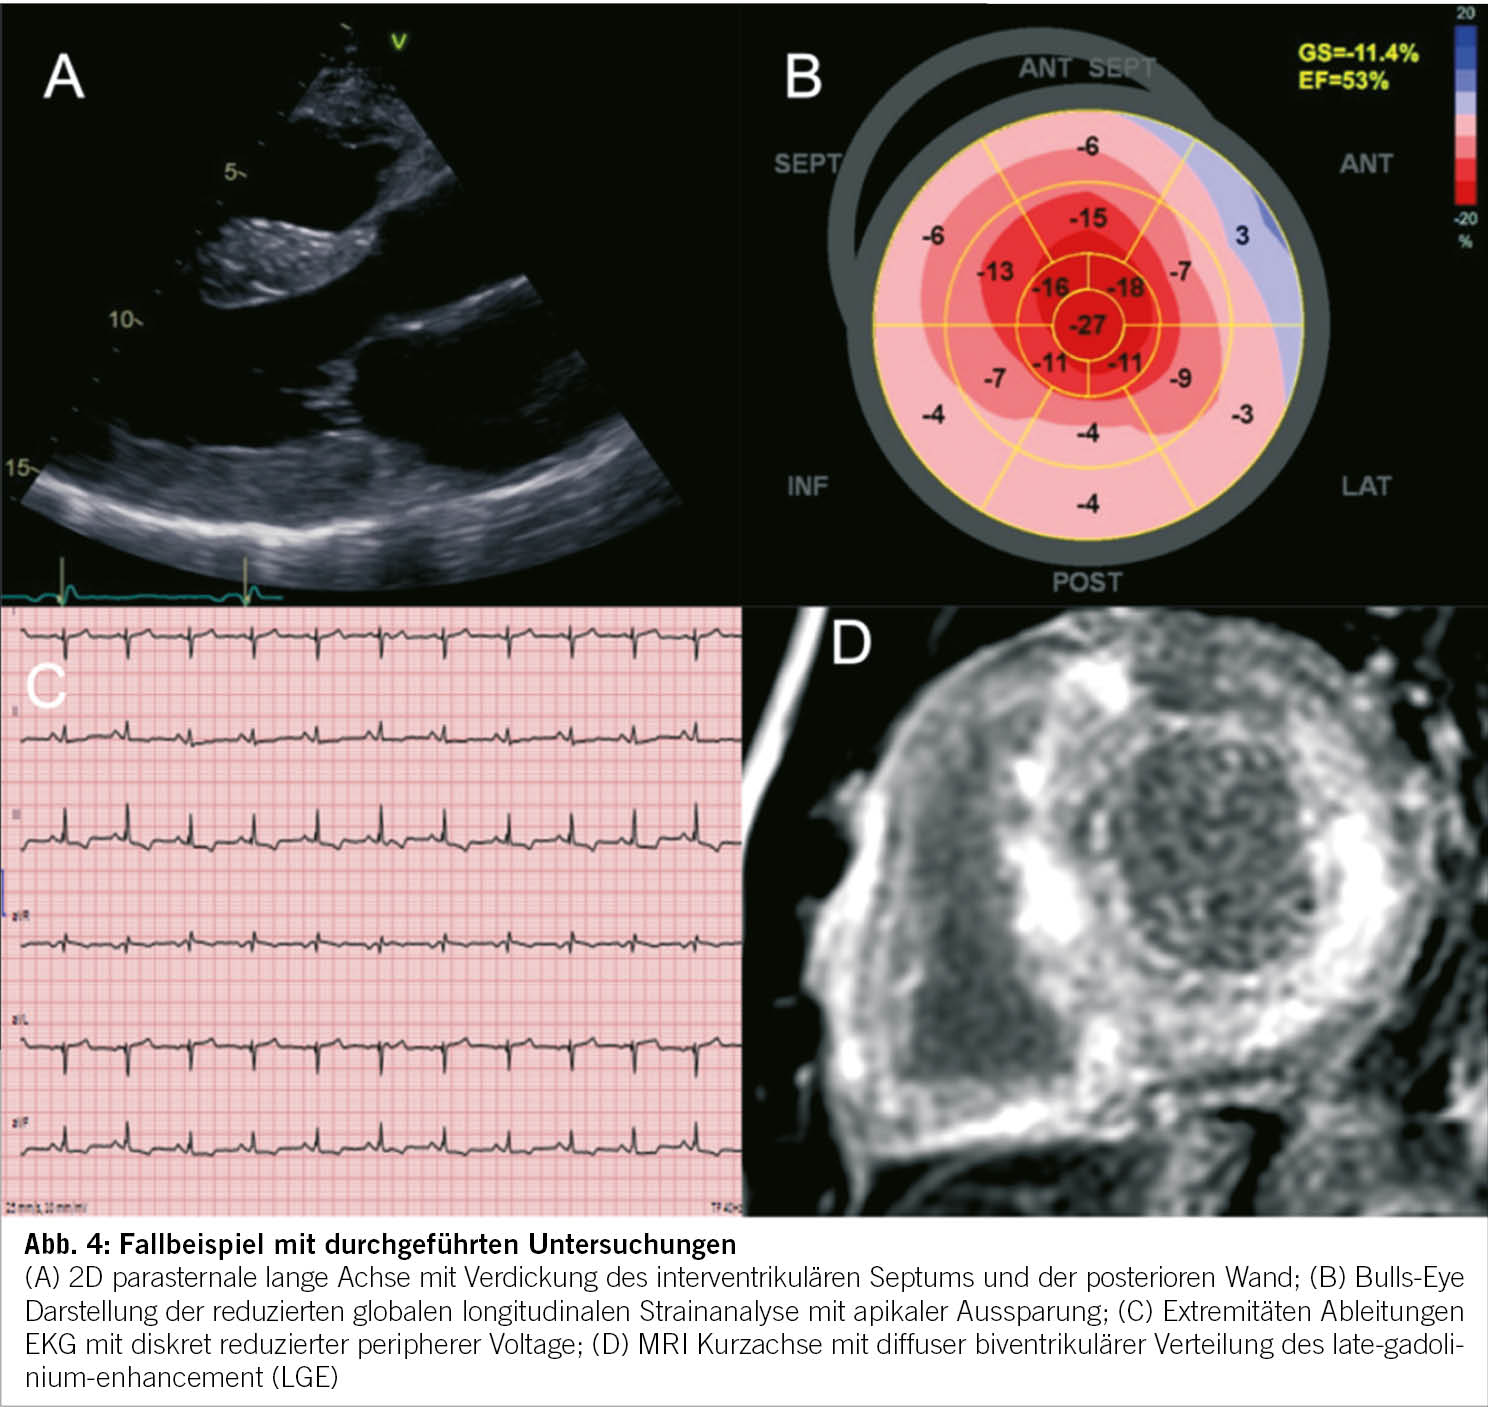

Folgendes Fallbeispiel eines 49-jährigen, männlichen Patienten mit progredienter Dyspnoe ist eine Illustration des diagnostischen Leitfadens. In der medizinischen Vorgeschichte sind eine unklare Niereninsuffizienz und ein bilaterales Karpaltunnelsyndrom bekannt. Die Familienanamnese ist bezüglich kardiovaskulärer Erkrankungen unauffällig. In der körperlichen Untersuchung fallen vor allem ein verbreiteter Herzspitzenstoss und ein vierter Herzton auf. Die pathologischen Werte in der Laboruntersuchung sind: Kreatinin 130umol/l, Troponin 46ng/l, NTproBNP 1700ng/l. Im 12-Kanal-EKG werden ein normokarder Sinusrhythmus, normale Zeitindices, ein Linkslagetyp, ST-Senkungen inferior und diskrete periphere Niedervoltage beobachtet. Die Echokardiographie zeigte einen konzentrisch verdickten linken Ventrikel mit erhaltener systolischer Funktion und schwerer diastolischer Dysfunktion mit restriktivem Füllungsmuster. Im Herz-MRI wurde eine diffuse, teils transmurale Fibrose beider Ventrikel und Vorhöfe dargestellt (Abbildung 4). Nach dieser Standortbestimmung gehen wir von einem Mischphänotyp der HCM und RCM aus. Die Bildgebung ist in diesem Fall sehr suggestiv für eine kardiale Amyloidose. Für die weitere Differentialdiagnose der Amyloidose wurden weitere Laboruntersuchungen (Immunfixation Serum und Urin) und eine weitere Bildgebung (99mTc-DPD- Szintigraphie) veranlasst. Infolge fehlender Hinweise für eine Plasmazelldyskrasie und Nachweis einer ausgeprägten Radionukleidanreicherung im linksventrikulären Myokard konnte die Diagnose einer Transthyretin Amyloidose gestellt werden. Aufgrund des sehr frühen Krankheitsauftretens erfolgte auch eine bioptische Sicherung der Diagnose mittels Endomyokardbiopsie. Nach einer genetischen Testung konnte eine genetische Form der Transthyretin Amyloidose ausgeschlossen werden, was wiederum für die Familie wichtig ist. Die genaue Stellung der Diagnose ermöglichte den Beginn einer Transthyretin-stabilisierenden Therapie.